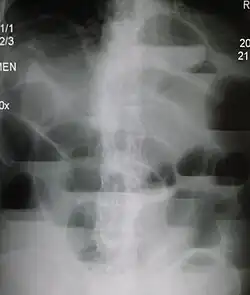

Ча́ши Кло́йбера — патогномоничный (специфический для конкретной патологии и только для неё) рентгенологический симптом кишечной непроходимости. Обусловлен наличием раздутых участков кишки, наполненных частично жидкостью, частично газом. Проявляется картиной «перевернутых чаш» с горизонтальным уровнем жидкости на снимке брюшной полости при вертикальном положении пациента[1][2].